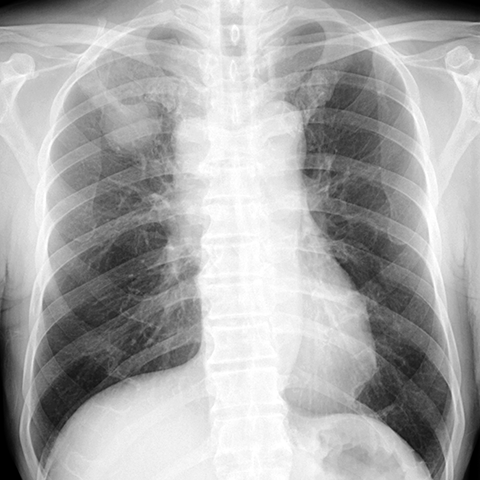

Mediastinal Lymphadenopathy, Lung Cancer (PA CXR) [1 of 3]